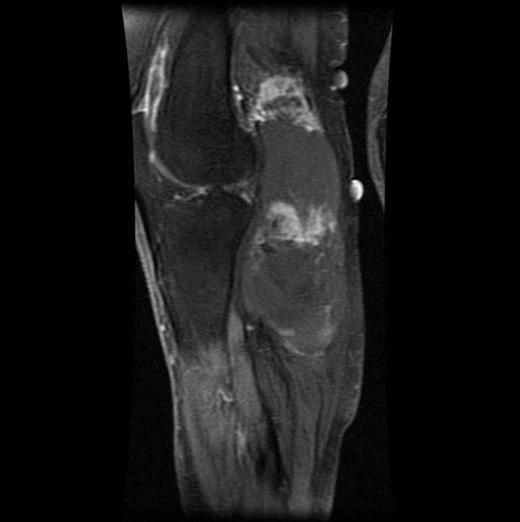

The MRI scan of the right knee (Figs 2 and 3) with gadolinium-enhancement showed a large mass lesion in the posterior aspect of the right knee extending into the popliteal fossa and into the upper third of the right leg having appearance of bursal pathology. Post gadolinium images showed evidence of circumferential rim enhancement but no internal enhancement indicating the presence of a fluid filled lesion. The mass (Figs 4 and 5) measured ∼8.39 × 6.14 × 12.72 cm and was seen between semimembranosus and biceps femoris muscles. There was no evidence of any infiltration of either the sciatic nerve or the popliteal vessels. A likely diagnosis of complicated synovial cyst with a differential diagnosis of haematoma was reported and a provisional diagnosis of Baker's cyst was established.

Post gadolinium-enhanced MRI image showing circumferential lesion.